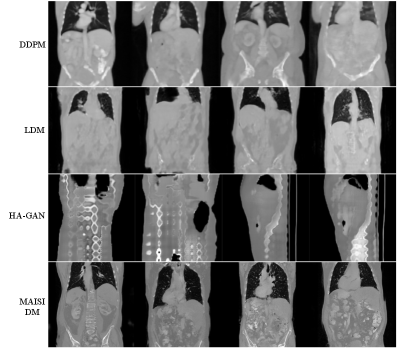

Synthesis quality. We assess the synthesis quality of the standalone MAISI DM by conducting comparisons with several established baseline methods, including DDPM [ho2020denoising], LDM [rombach2022high], and HA-GAN [sun2022hierarchical]. The first evaluation focuses on comparing the fidelity of images generated by our model against those produced by the HA-GAN [sun2022hierarchical], utilizing its publicly available trained weights111https://github.com/batmanlab/HA-GAN. Given that HA-GAN  [sun2022hierarchical] specifically targets CT images of the chest region, we curate a collection of chest CT datasets for this analysis, including MSD Lung Tumor [antonelli2022medical] (MSD Task06), LIDC-IDRI [hancock2016lung], and TCIA COVID-19 [harmon2020artificial]. These datasets provide a diverse range of imaging conditions and pathology, enriching the comparative study. We use the Fréchet Inception Distance (FID) [heusel2017gans] as the metric for evaluating the similarity between the distributions of generated images and real counterparts from varied sources. Table 2 presents the average FID for both real and synthesized images across the three datasets. Notably, the MAISI DM significantly outperforms HA-GAN [sun2022hierarchical] in all datasets, demonstrating its capability to generate images with a much closer appearance to real data.

In addition, we retrain all baseline methods using our large-scale datasets, described in Sec. 4.1. For a more comprehensive evaluation of synthesis quality, we utilize an unseen dataset autoPET 2023 [gatidis2022whole] as the reference to conduct synthesis quality evaluation. This dataset encompasses whole-body CT scans from patients with various types of cancer and negative controls. Results in Table 3 demonstrate that our MAISI DM surpasses the retrained baseline models in generating high-quality images in the external evaluation. Fig. 4 presents a visual comparison illustrating that the high-resolution images synthesized by the MAISI DM show improved detail and a more precise representation of global anatomical structures compared to baseline methods.

Figure 4: Qualitative comparison of generated images between retrained baseline methods using our large-scale datasets and MAISI DM.